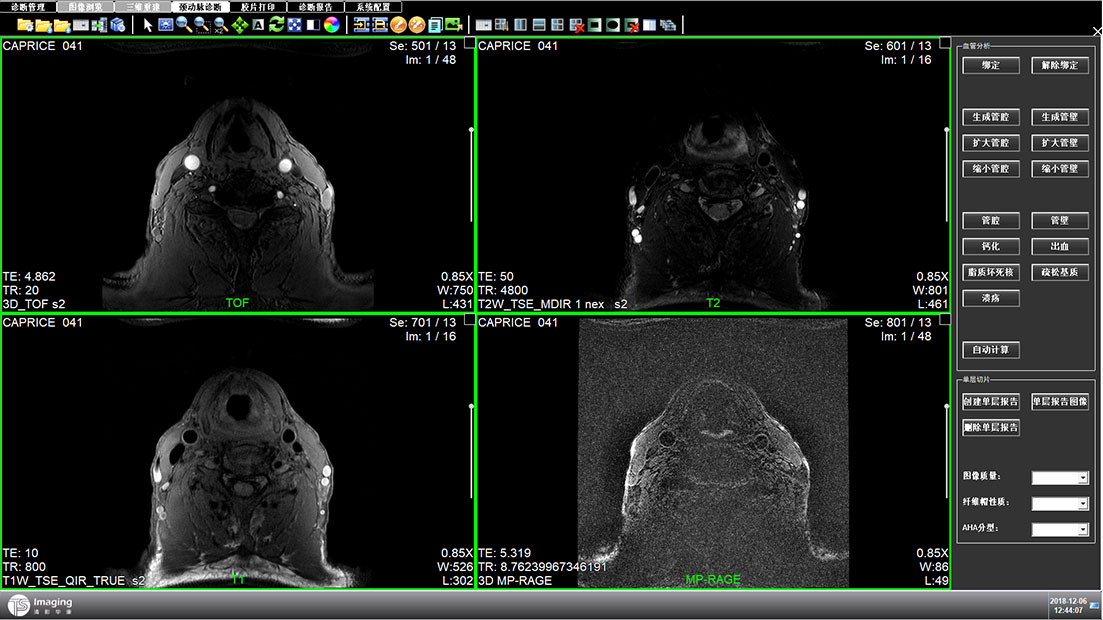

頸動(dòng)脈診斷頁(yè)面

頸動(dòng)脈診斷頁(yè)面整體布局和三維重建比較相似,最大的區(qū)別是右側(cè)的操作區(qū)域,血管分析都為按鍵操作,通過(guò)間隔的大小分成三部分。單層切片除了按鍵還有下拉菜單的操作。